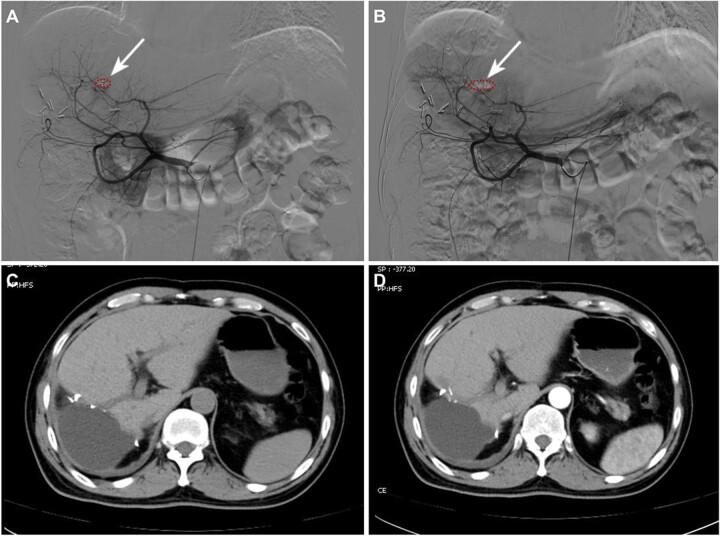

The most common treatment of spontaneous tumor rupture hemorrhage (STRH) is transcatheter arterial embolization (TAE) followed by liver resection, and surgical navigation using near-infrared fluorescence is effective method for detecting hidden lesions and ill-defined tumor boundaries. However, due to the blockage of the tumor-supplying artery after effective TAE treatment, it is difficult to deliver sufficient fluorescent probes to the tumor region. In this study, we report on the successful application of superstable homogeneous intermixed formulation technology (SHIFT) in precise conversion hepatectomy for ruptured hepatocellular carcinoma (HCC). A homogeneous lipiodol-ICG formulation obtained by SHIFT (SHIFT-ICG) was developed for clinical practice for STRH. A ruptured HCC patient received the combined protocol for embolization and fluorescence surgical navigation and exhibited excellent hemostatic effect. Lipiodol and ICG were both effectively deposited in the primary lesion, including a small metastatic lesion. In follow-up laparoscopic hepatectomy, SHIFT-ICG could clearly and precisely image the full tumor regions and boundaries in real time, and even indistinguishable satellite lesions still expressed a remarkable fluorescence intensity. In conclusion, the simple and green SHIFT-ICG formulation can be effectively used in emergency embolization hemostasis and later precise fluorescence navigation hepatectomy in patients with ruptured HCC bleeding and has high clinical application value.

自发性肿瘤破裂出血(STRH)最常见的治疗方法是经导管动脉栓塞术(TAE),随后进行肝切除术,而使用近红外荧光的手术导航是检测隐匿性病变和边界不清的肿瘤边界的有效方法。然而,由于有效的TAE治疗后肿瘤供血动脉被阻断,难以将足够的荧光探针输送到肿瘤区域。在本研究中,我们报告了超稳定均匀混合制剂技术(SHIFT)在破裂肝细胞癌(HCC)精准转化肝切除术中的成功应用。通过SHIFT获得的均匀碘油-吲哚菁绿制剂(SHIFT-ICG)被开发用于STRH的临床实践。一名破裂HCC患者接受了栓塞和荧光手术导航联合方案,显示出优异的止血效果。碘油和吲哚菁绿均有效沉积在原发性病变中,包括一个小转移灶。在后续的腹腔镜肝切除术中,SHIFT-ICG能够实时清晰、精确地成像整个肿瘤区域和边界,甚至难以区分的卫星病灶仍表现出显著的荧光强度。总之,简单且绿色的SHIFT-ICG制剂可有效用于破裂HCC出血患者的急诊栓塞止血及后续精准荧光导航肝切除术,具有较高的临床应用价值。